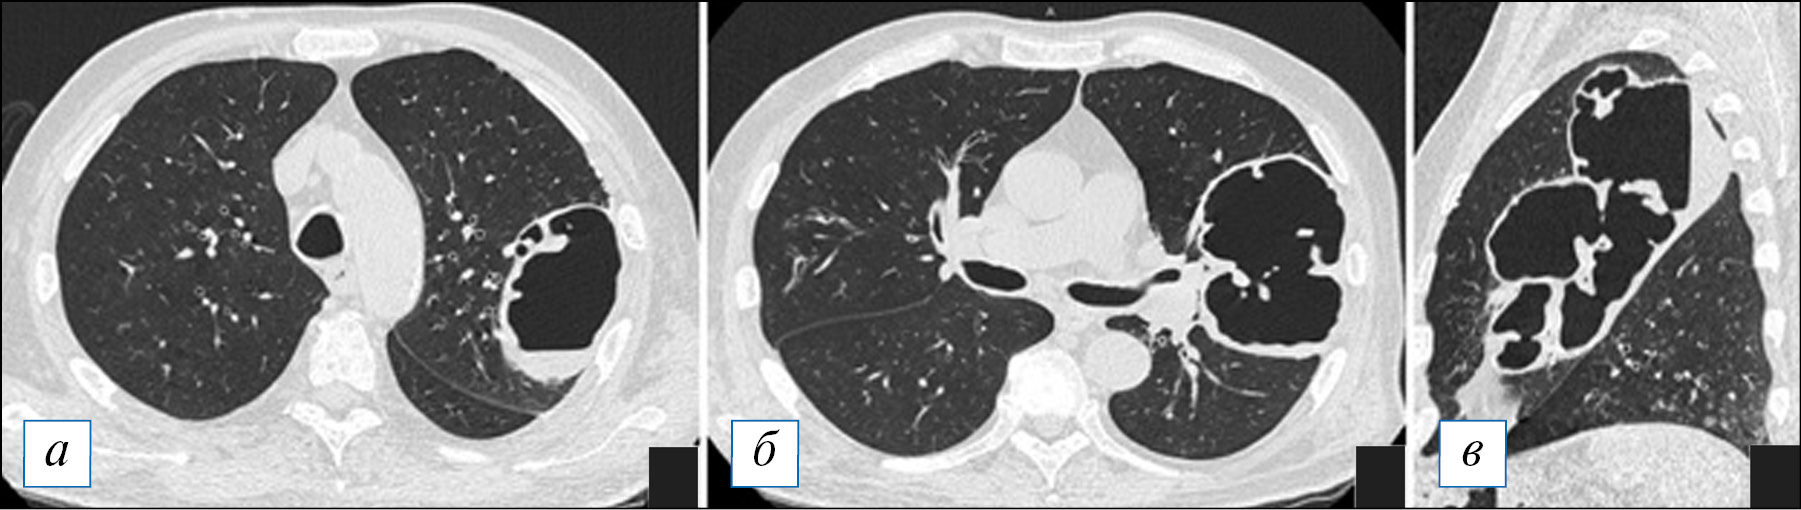

Рис. 9. Компьютерная томография органов грудной клетки в аксиальной проекции (а–г). Типичная картина острого абсцесса. В верхней доле справа имеется полость с содержимым, при этом наружная и внутренняя стенка полости с достаточно четкими контурами, перикавитарная инфильтрация выражена слабо. [Изображения из архива авторов]. / Fig. 9. Chest CT, axial projection (а–г). A typical picture of an acute abscess. In the upper lobe on the right there is a filled cavity the outer and inner wall of the cavity having fairly clear contours, pericavitic infiltration is poorly expressed. [Images from the authors’ archive].

Рис. 10. Компьютерная томография органов грудной клетки в аксиальной (а, б) и сагиттальной (в) проекциях. Многокамерный «лестничный» острый абсцесс в верхней доле левого легкого. В абсцессе имеется незначительное количество содержимого, инфильтрация вокруг полости отсутствует. [Изображения из архива авторов]. / Fig. 10. Axial (а, б) and sagittal (в) chest CT images. Multi-chamber «ladder» acute abscess in the upper lobe of the left lung. There is a small amount of fluid in the abscess, and there is no infiltration around the cavity. [Images from the authors’ archive].